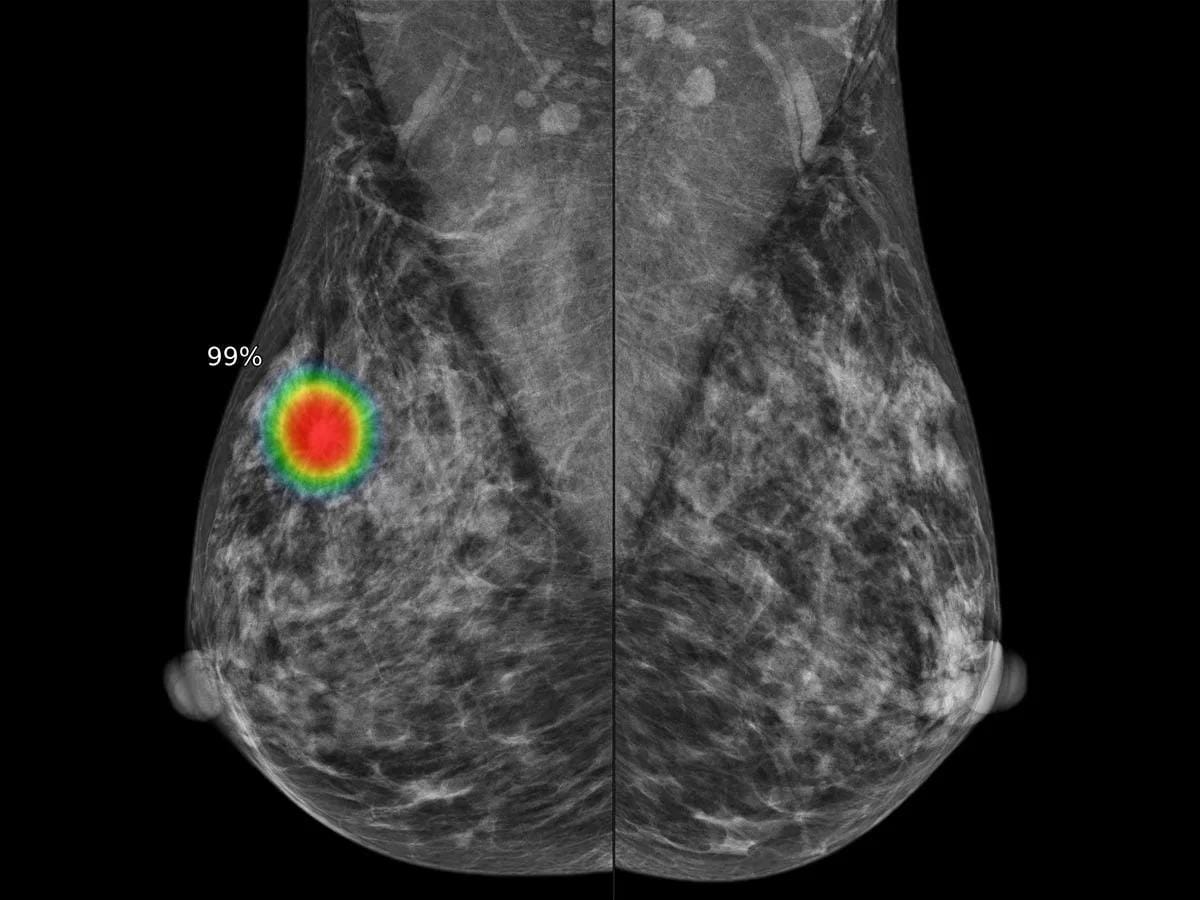

La investigación liderada por Google y el NHS marcó un punto de inflexión en la lucha contra el cáncer de mama. El sistema experimental analizó las mamografías de 115.973 mujeres y detectó una mayor cantidad de casos invasivos que los métodos convencionales.

La tasa de detección aumentó de 7,54 a 9,33 por cada 1.000 pacientes cuando la herramienta actuó como segundo lector.

Este avance, según resaltó Europa Press, permitió identificar el 25% de los llamados «cánceres de intervalo», aquellos que permanecieron ocultos en exploraciones previas y que suelen manifestarse solo ante síntomas graves.

El estudio demostró que la inteligencia artificial redujo significativamente los falsos positivos, especialmente en mujeres que acudieron a su primera mamografía.